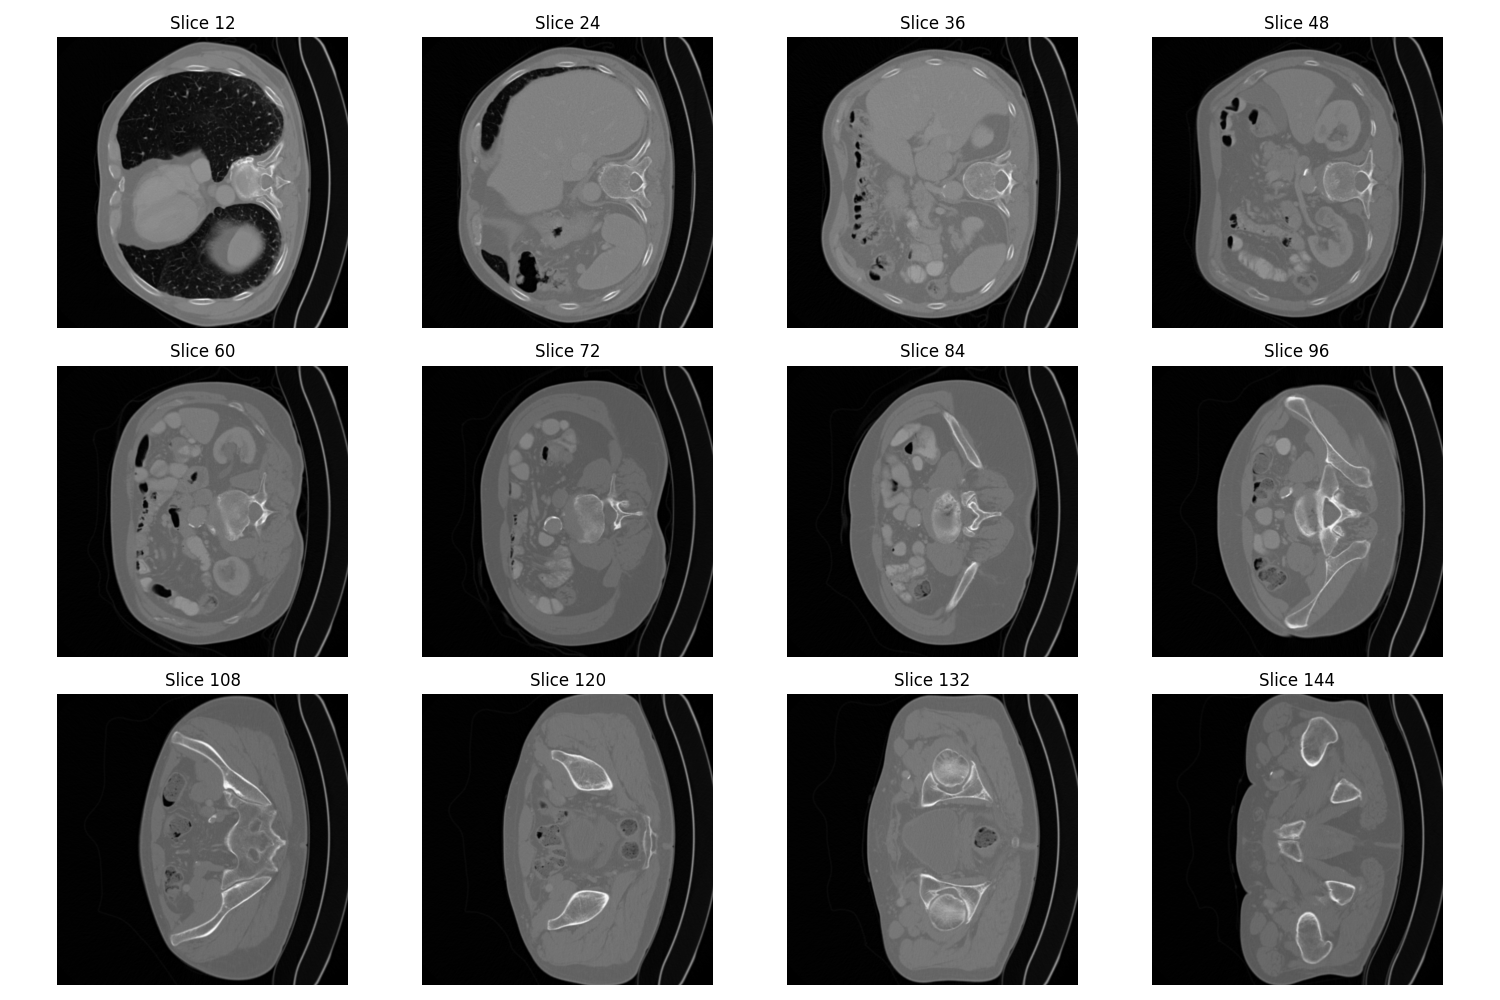

Examples of kidney tumors from different angles

Montage image of a malignant tumor

Montage image of a benign tumor